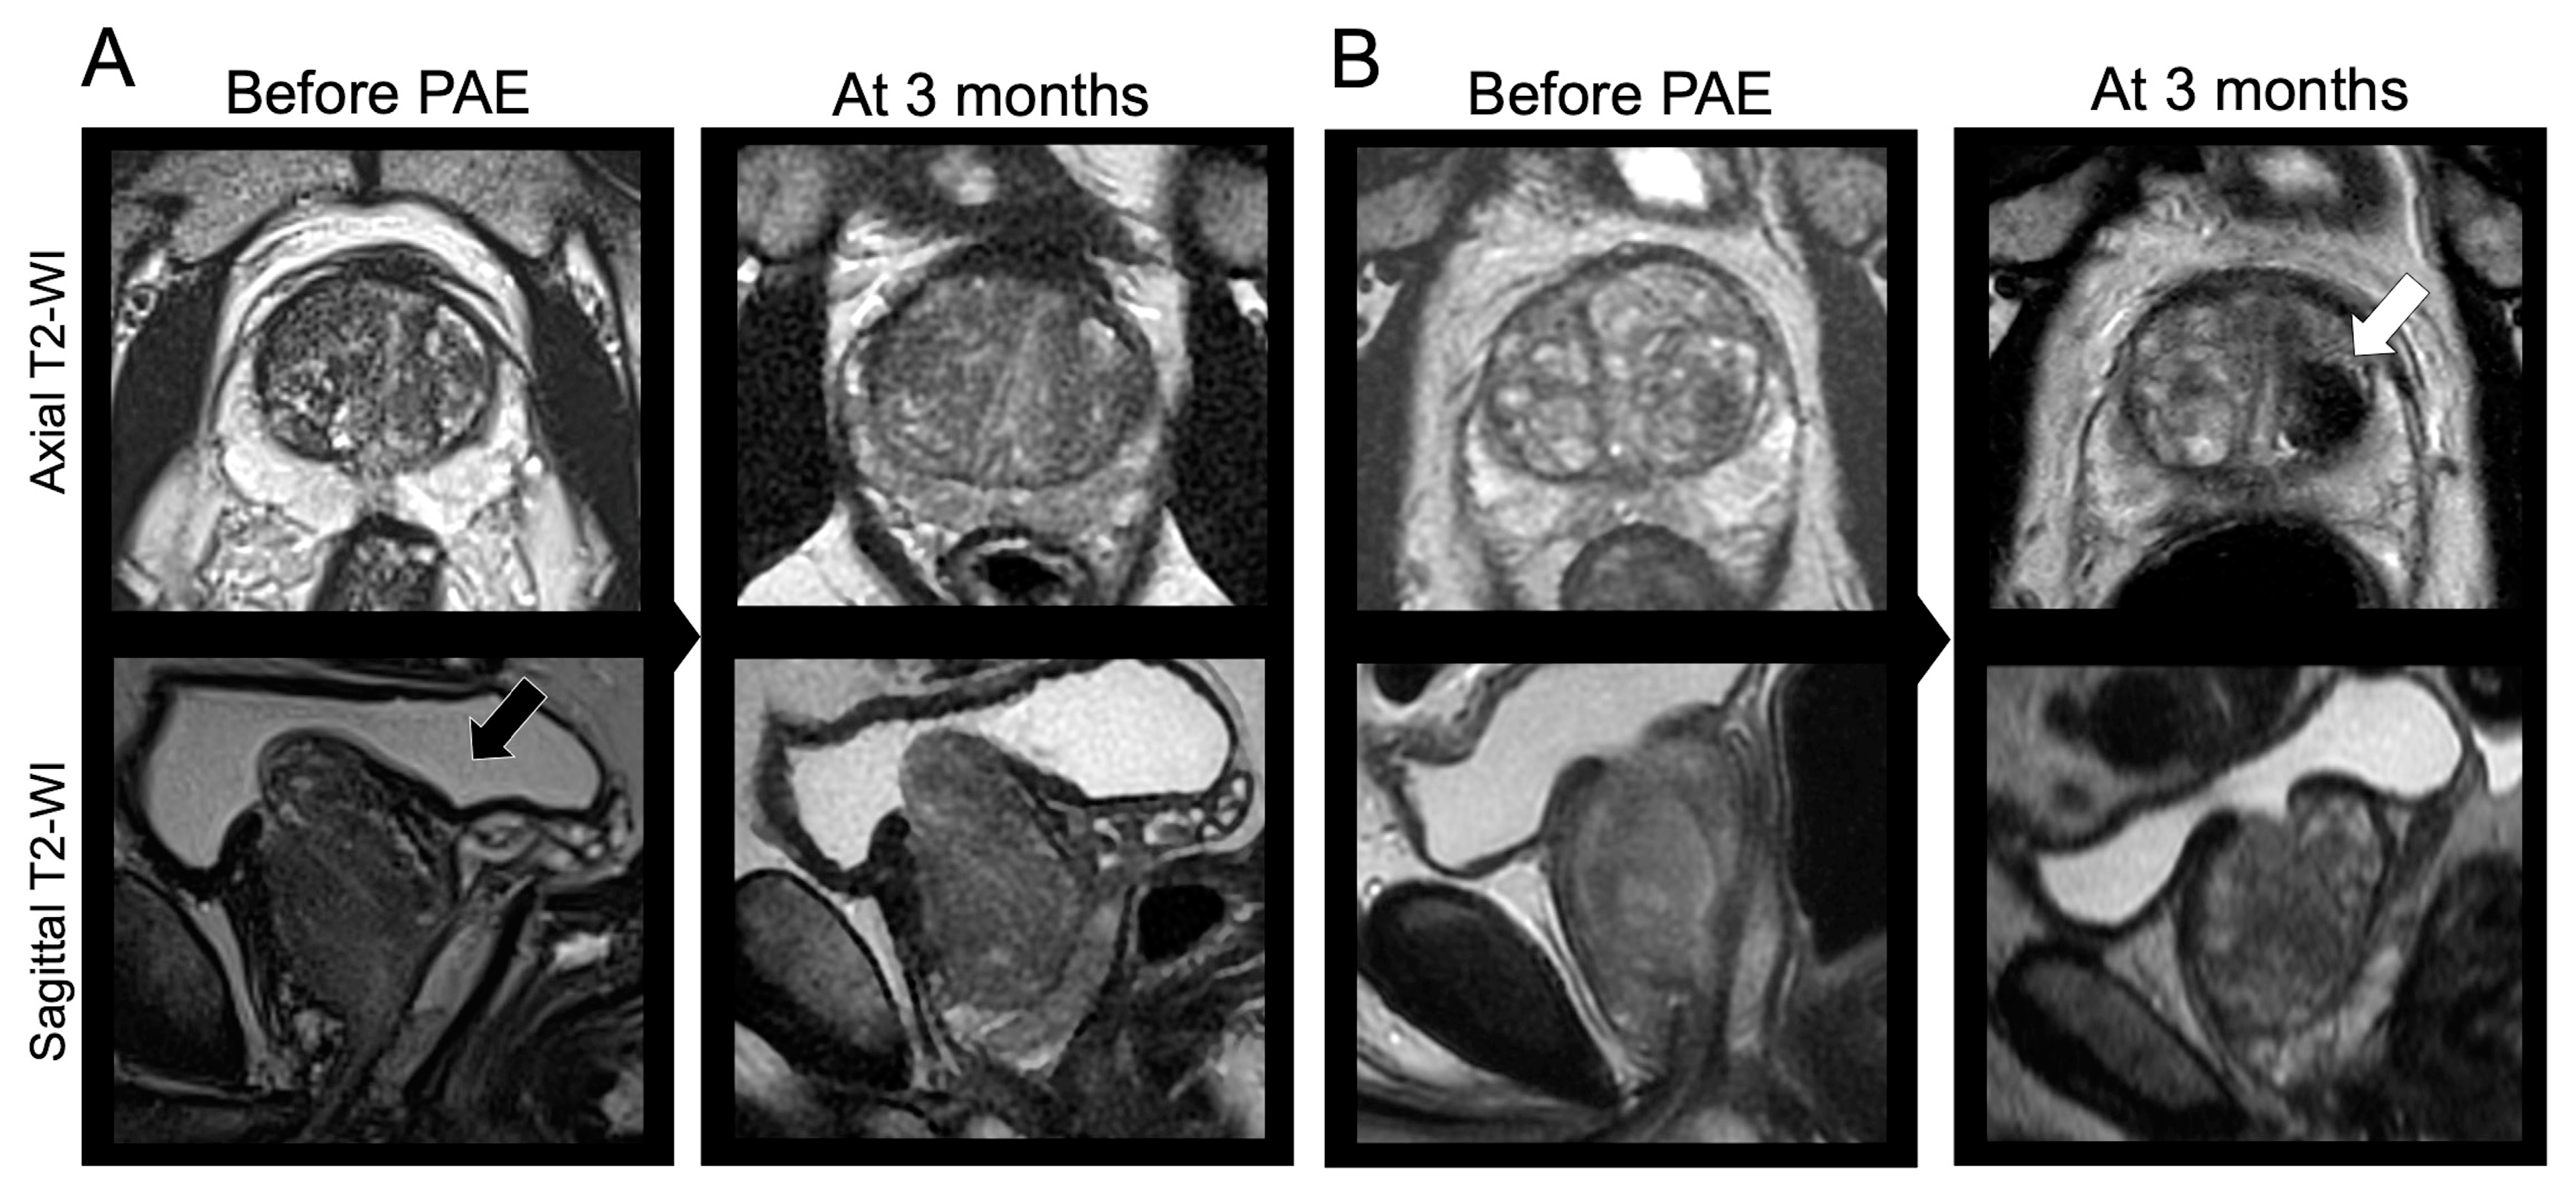

Figure 7 illustrates those findings through two opposite examples.

Figure 7. Clinical examples. (A) A 54-year-old male underwent a bilateral prostate artery embolization (PAE) with glue and microparticles for lower urinary tract symptoms (LUTS) due to benign prostate hypertrophy (BPH) with initial IPSS = 19 and initial QOL = 5. The prostate was classified as Wasserman type 2 (black arrow). The relative change in IPSS at 3 months was +21.9% (>−35%). The patient declared no relief from his symptoms at 3 months and 2 years following PAE. (B) A 64-year-old male underwent a bilateral PAE with microparticles for LUTS due to BPH with initial IPSS = 25 and initial QOL = 5, and a Wasserman type 1 prostate. At early revaluation, a prostate infarct was noticed (white arrow). The relative change in IPSS at 3 months was −92% (<−35%). The patient was satisfied with PAE and symptoms relief at 3 months, 2 years, and during his latest visit 38 months after PAE. Other abbreviation: WI: weighted imaging.